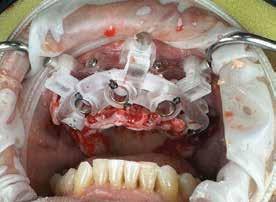

72 FDC 2026 Speaker: Full Arch Implant Reconstruction in the Digital Era: Past, Present and Future